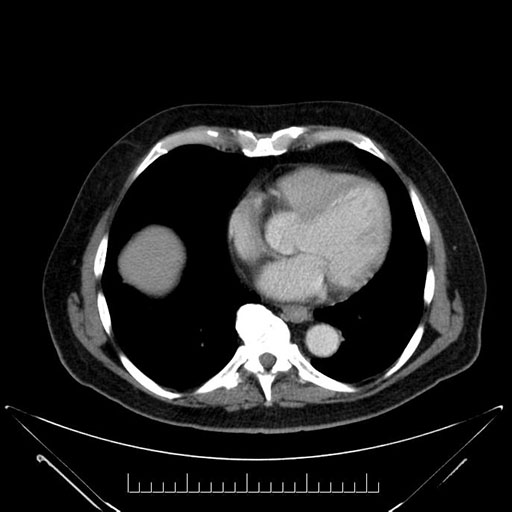

Whipple (pancreaticoduodenectomy) [case 7]

Axial - 3 months prior